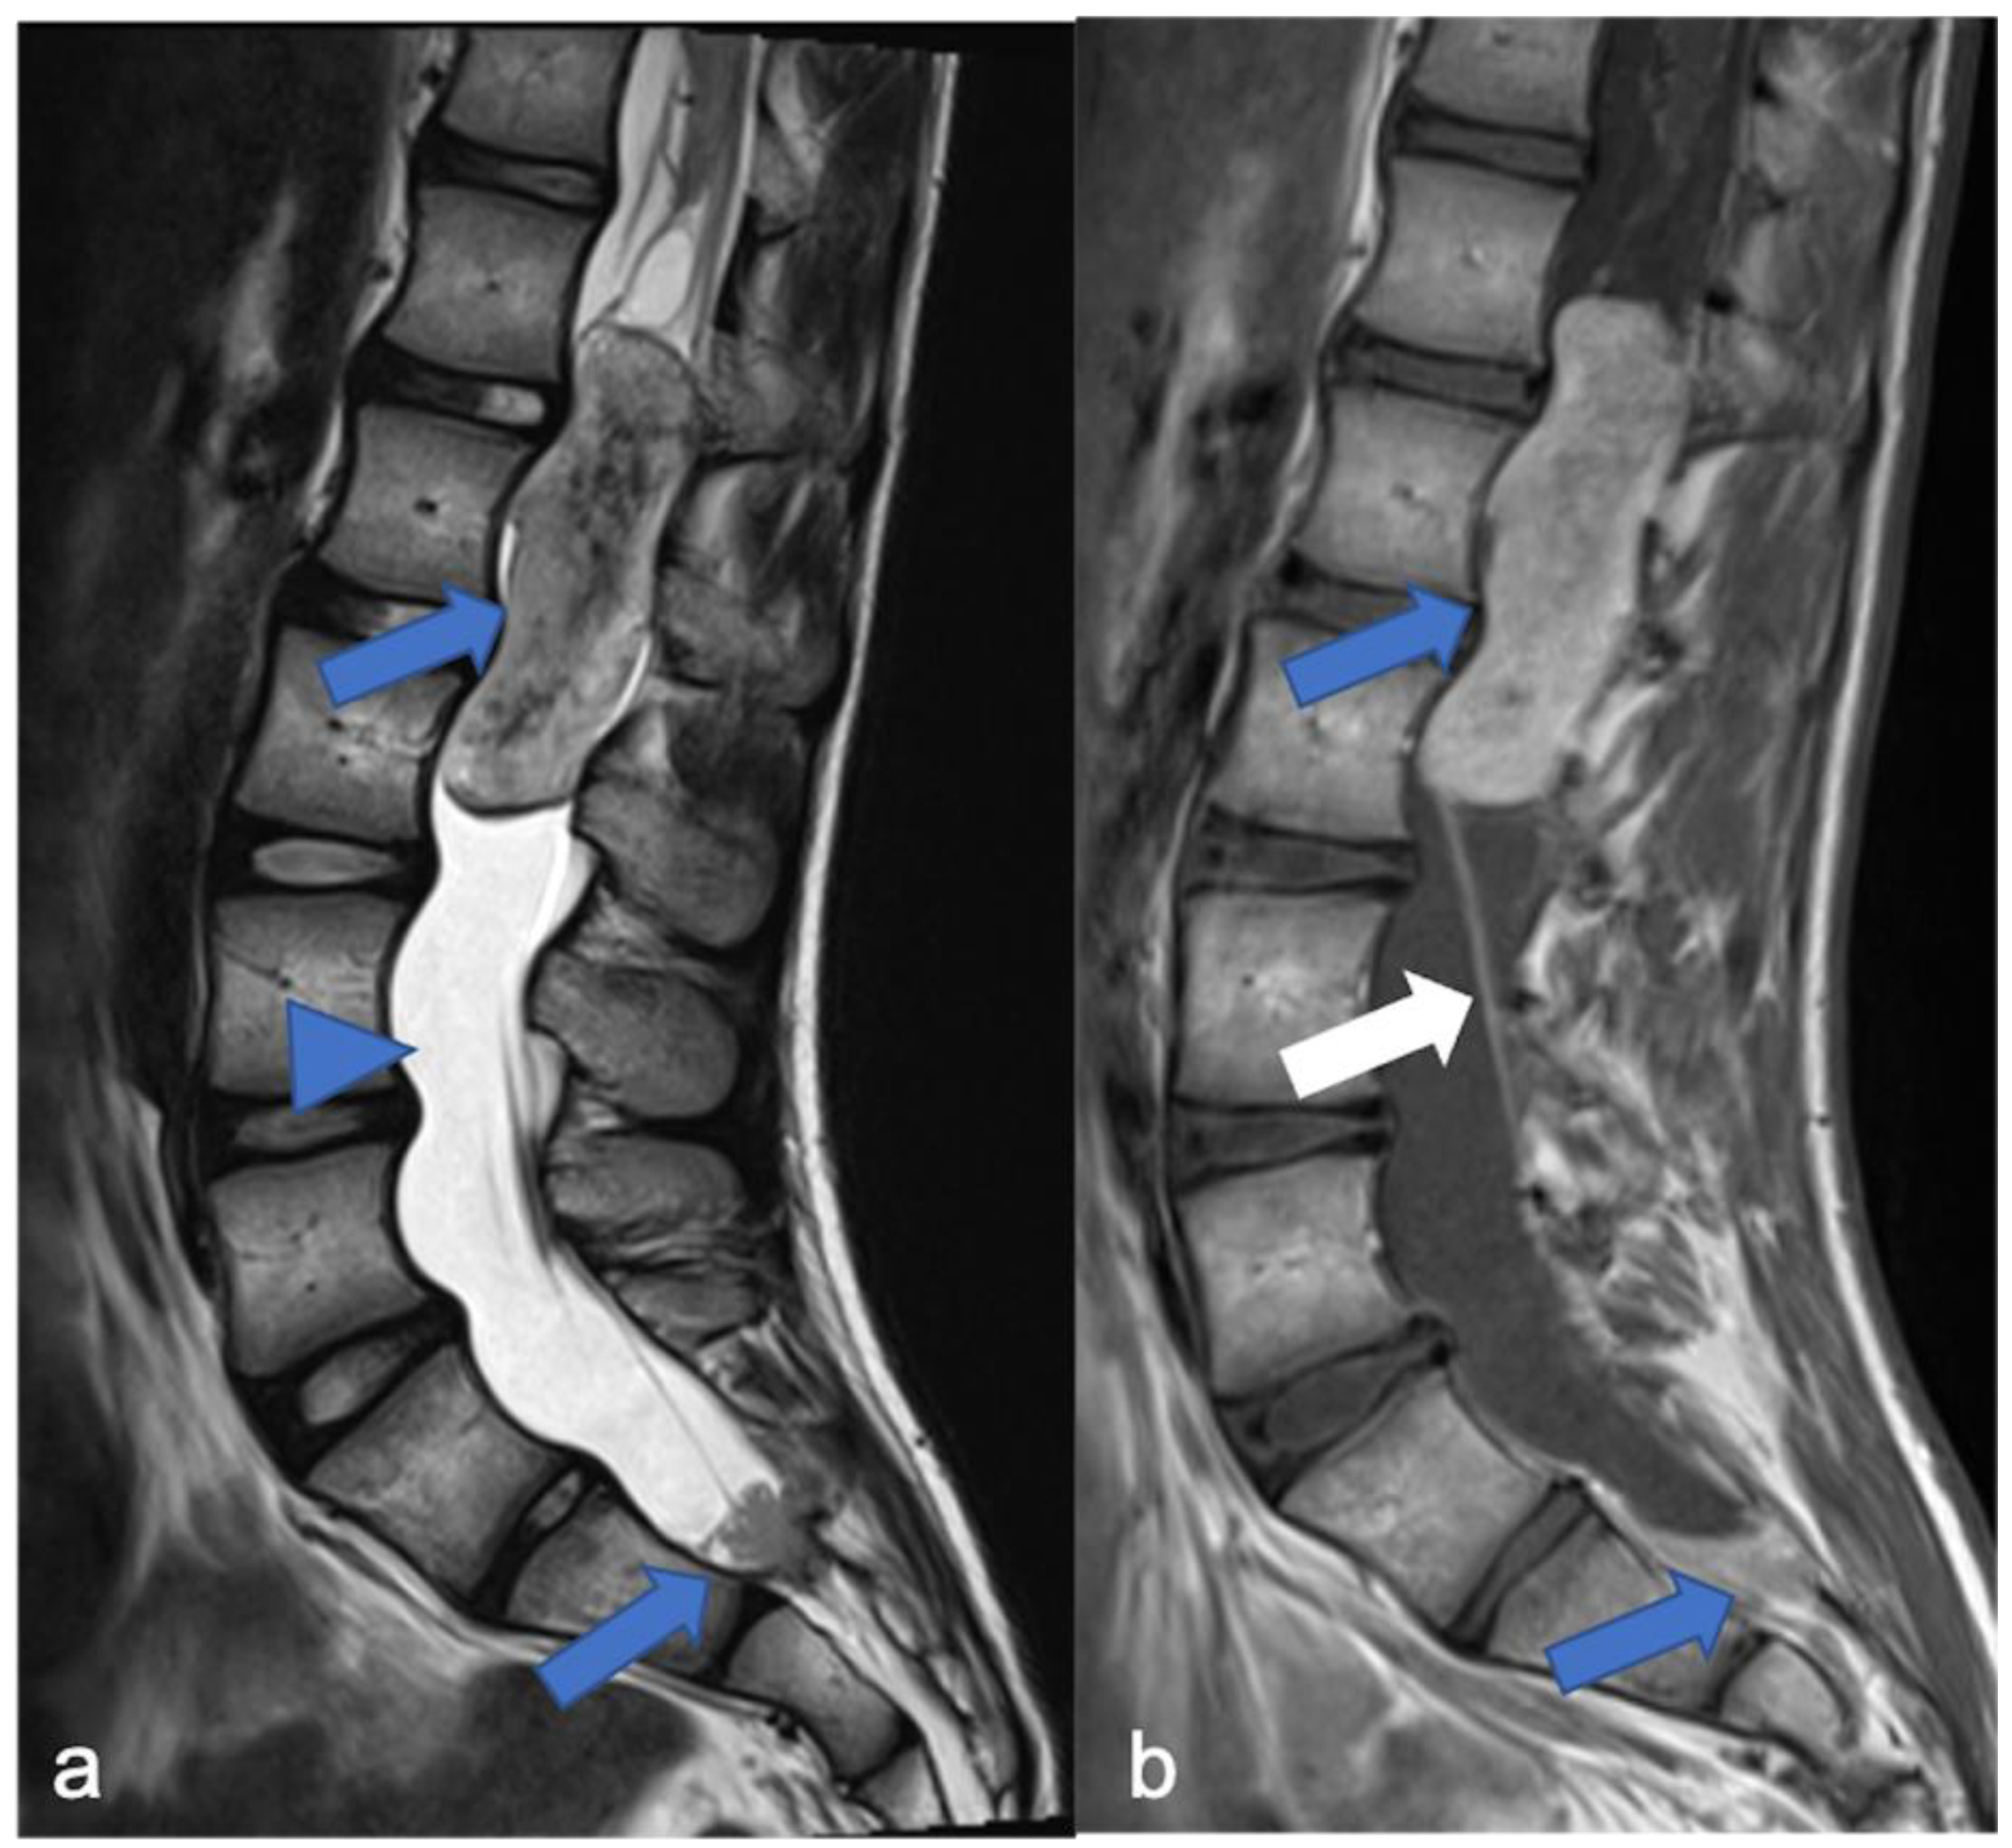

Figure 8.

Myxopapillary ependymoma in a fourteen-year-old child located in the lumbo-sacral region. Sagittal T2-weighted (a) and post-contrast T1-weighted (b) images demonstrate solid cranial and caudal enhancing components (blue arrows) and a pseudocystic non-enhancing component (arrowhead). The detail of the filum terminale is also highlighted (white arrow).